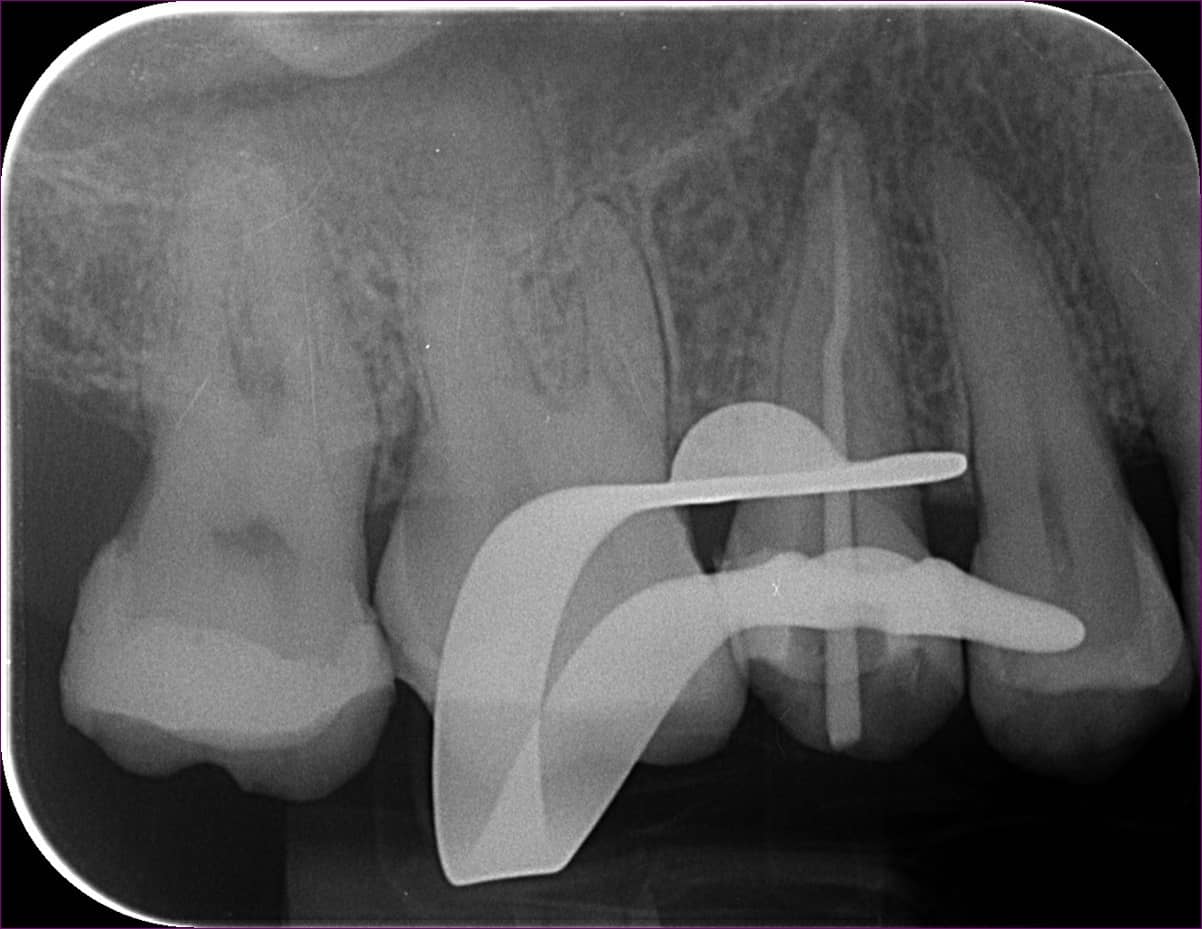

Mivel az eddig kezelt csatornában gond nélkül végig lehetett haladni, egyértelmű volt, hogy a másik darabka a másik csatornában található. Kis kutakodás után ezt is sikeresen megtaláltuk, és eltávolítottuk. igazolásképpen készült egy újabb kontrollröntgen.

A következő alkalommal alaposan átfertőtlenítettük a csatornákat. Itt már láttuk is, hogy tényleg közös utolsó szakasszal rendelkeznek.

Protokoll szerint ismét röntgenfelvétel következett, mellyel ellenőriztük a kiválasztott későbbi gyökértömő pálcika méretét.